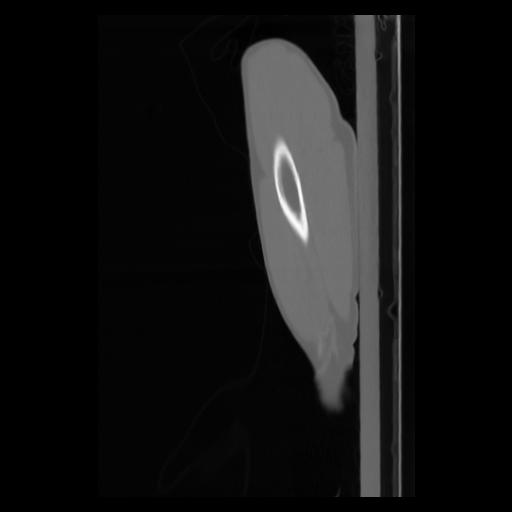

30 CUERPO,CE,Sagittal,3.000,CUERPO,Sagittal,